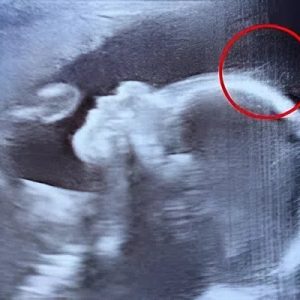

The doctors did not understand why the baby never came out of the womb!

A mother’s instincts proved lifesaving for Melbourne resident Lilly Munro. At 24 weeks pregnant, she felt something was wrong with her unborn son, Lennox, and rushed to…